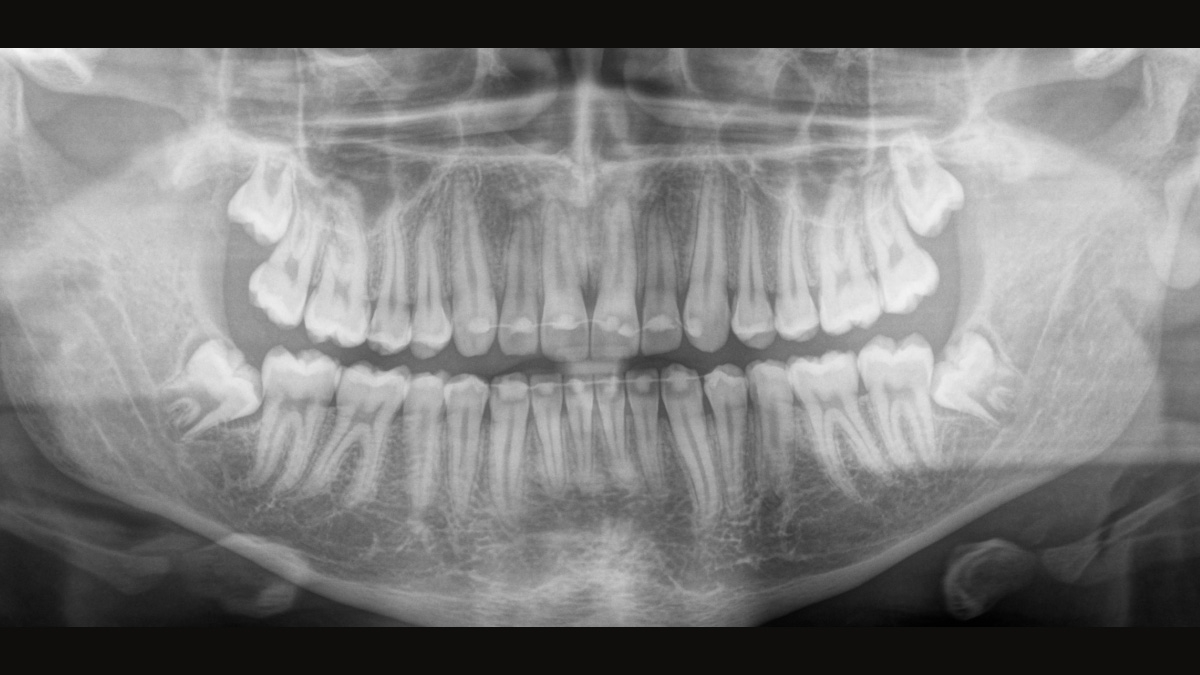

We developed a 10-point concept for easy patient positioning and X-ray imaging. Our concept is primarily about two things: high image quality and comfort for the patient and the assistant. This concept supports and provides the tools needed to ensure high-quality images for treatment analysis and focuses on ergonomics and comfort for the patient and assistant.

The patented bite block technology, for example, automatically establishes the correct inclination of the patient's head, positioning the patient in the occlusal plane, partnering with the 3 point head fixation and firm handles to ensure stable positioning-limiting unnecessary correction scans.